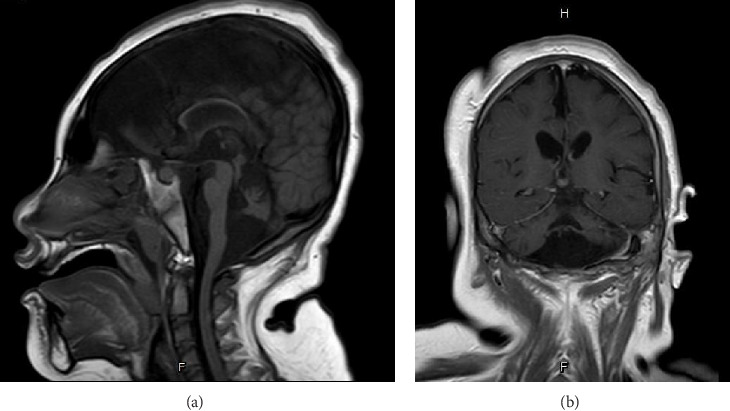

III型桥小脑发育不全(PCH3)是一种罕见的常染色体隐性神经退行性疾病,与PCLO基因突变有关,以前仅在阿曼人群中报道过。它表现为进行性小头畸形、顽固性癫痫、视神经萎缩和严重的发育迟缓。在这里,我们报告了首例记录在案的PCH3病例,一名8岁的泰国女孩患有两种新颖的PCLO截断突变。患者从2个月大开始出现顽固性癫痫和严重的整体发育迟缓。全外显子组测序发现PCLO基因存在复合杂合突变:c.9018_9037del (p.Tyr3007Ter)和c.8456del (p.Ala2819GlufsTer2),这两个突变均来自杂合亲本。这些突变预计会导致短笛蛋白功能的丧失。该病例扩展了pclo相关PCH3的突变谱,并强调了先进分子诊断在理解和治疗这种罕见的神经退行性疾病中的重要性。由于缺乏治疗方法,早期遗传诊断对于指导患者护理和遗传咨询至关重要。

Pontocerebellar hypoplasia Type III (PCH3) is a rare, autosomal recessive neurodegenerative disorder linked to mutations in the PCLO gene, previously reported only in Omani populations. It presents with progressive microcephaly, intractable epilepsy, optic atrophy, and severe developmental delay. Here, we report the first documented case of PCH3 in an 8-year-old Thai girl with two novel PCLO truncation mutations. The patient presented with intractable epilepsy from 2 months of age and severe global developmental delay. Whole exome sequencing identified compound heterozygous mutations in the PCLO gene: c.9018_9037del (p.Tyr3007Ter) and c.8456del (p.Ala2819GlufsTer2), both of which were inherited from heterozygous parents. These mutations are predicted to result in a loss of Piccolo protein function. This case expands the mutational spectrum of PCLO-related PCH3 and highlights the importance of advanced molecular diagnostics in understanding and managing this rare neurodegenerative disorder. Given the lack of curative therapies, early genetic diagnosis is crucial in guiding patient care and genetic counseling.